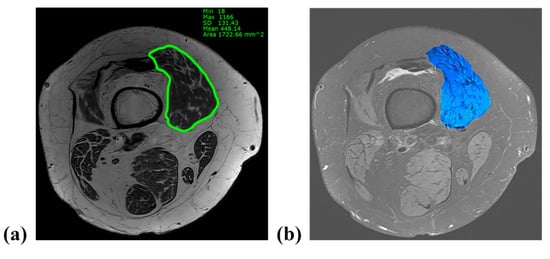

Patients underwent MRI (Magnetom Skyra; Siemens Medical Solutions, Erlangen, Germany) with the knee fully extended in the supine position and stabilized by a knee holder. During MRI, the knee joint (between 1/3rd of the distal femur and 1/3rd of the proximal tibia) was fully covered and contained axial slices of proton density (PD) and PD fat suppression at 2 mm intervals. The VM cross-sectional area (CSA) and the fat infiltration (FI) ratio were measured at the distal 10% level of the femoral length. This level has been previously reported to reflect the total quadriceps volume in patients with knee OA []. The femoral length was defined as the length from the distal end of the lesser trochanter to the superior surface of the patella on a full-length standing anteroposterior radiograph (Figure 2). On coronal MRI view, the level was identified from the superior surface of the patella and the corresponding axial slice was matched using 3D indicators of the picture archiving communication system (PACS; M6, Infinitt Healthcare, Republic of Korea). The VM CSA was acquired from the axial PD image after marking the VM margin using the embedded tools of the PACS software. To assess the FI ratio of the VM, the marked area on the PD slice was transferred to the corresponding PD fat-suppression slice and the intramuscular fat signal within the area was confirmed by comparing the PD and PD fat-suppression slices. Thereafter, the area was color-mapped using 16 different colors for each signal. Color pixels corresponding to the signal of the fat tissue were extracted, and the FI ratio was defined as the percentage of the pixels of the fat tissue to the sum of the pixels of VM (Figure 3). The hip–knee–ankle (H–K–A) angle was determined as the angle formed by the mechanical axis of the femur and the tibia on full-length standing anteroposterior (AP) radiographs. To classify the severity of OA, the tibiofemoral joint was evaluated using the Kellgren–Lawrence scale in standing AP and lateral radiographs as follows: grade I, doubtful narrowing of the joint space and possible osteophytic lipping; grade II, definite osteophytes and possible narrowing of the joint space; grade III, moderate multiple osteophytes and definite narrowing of the joint space; and grade IV, large osteophytes-marked narrowing of the joint space [].

Figure 3.

Measurement of cross-sectional area (CSA) and fat infiltration (FI) ratio on axial magnetic resonance imaging. (a) The vastus medialis (VM) CSA was acquired from the axial proton density image after marking the VM margin using the embedded tools of the picture archiving communication system software. (b) The area corresponding to the VM was color-mapped with 16 different colors for each signal. Color pixels derived from the fat signal were extracted, and the FI ratio was defined as the percentage of the number of fat pixels to the sum of the VM pixels.